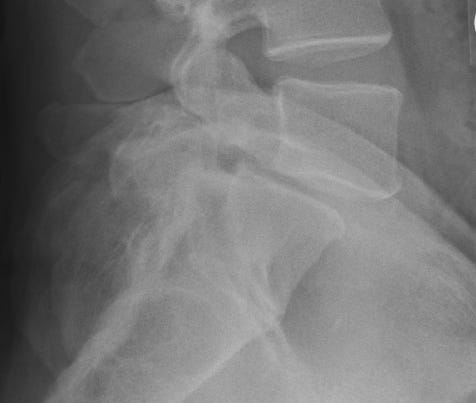

See the slip? That's where my numbness comes from.